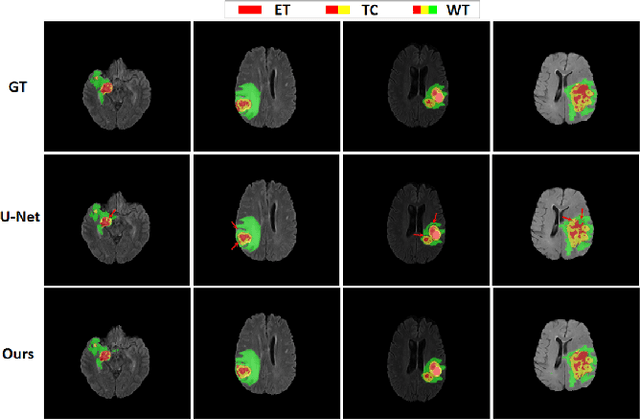

Abstract:A glioma is a malignant brain tumor that seriously affects cognitive functions and lowers patients' life quality. Segmentation of brain glioma is challenging because of interclass ambiguities in tumor regions. Recently, deep learning approaches have achieved outstanding performance in the automatic segmentation of brain glioma. However, existing algorithms fail to exploit channel-wise feature interdependence to select semantic attributes for glioma segmentation. In this study, we implement a novel deep neural network that integrates residual channel attention modules to calibrate intermediate features for glioma segmentation. The proposed channel attention mechanism adaptively weights feature channel-wise to optimize the latent representation of gliomas. We evaluate our method on the established dataset BraTS2017. Experimental results indicate the superiority of our method.